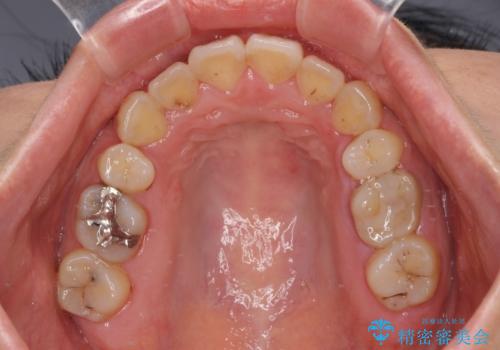

- ハーフリンガル

目立たない装置を希望されたので、上顎が裏側装置のハーフリンガルを選択し、上下左右の小臼歯(計4歯)を抜歯して矯正治療を行うこととしました。

デコボコの解消までは非常にスムーズでしたが、咬合力が強いためか、スペースを閉じるまでに長い期間を要しました。

矯正治療途中にインプラント埋入と仮歯の装着を行ったことで、しっかりとした奥歯の咬み合わせで終了させることができました。